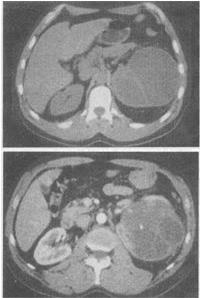

女,48岁,左腰部胀痛不适2个月余,根据所示图像,最可能的诊断是()。

A:左侧囊性肾癌

B:左侧肾囊肿

C:左侧多囊肾

D:左侧肾脓肿

E:左侧肾积水